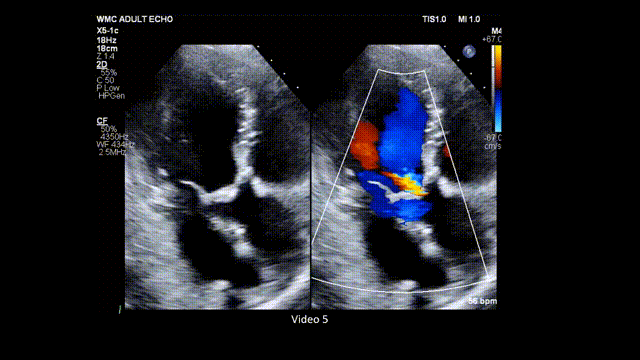

7、心尖五腔心切面: 在主动脉瓣处的彩色多普勒显示主动脉瓣狭窄引起的彩色镶嵌血流(mosaic color flow)模式,且可显示主动脉瓣反流(aortic regurgitation,AR)。应确认湍流起始位置,确保湍流源自瓣膜层面,而非瓣下(如主动脉瓣下隔膜或肥厚型心肌病所致左室流出道梗阻)或瓣上位置(图8,视频5)。

图8. 心尖五腔心切面评价主动脉瓣狭窄(有和彩色多普勒对比)

心尖五腔心切面结合主动脉瓣处彩色多普勒,用于评估流出道梗阻所致狭窄性彩色镶嵌血流模式以及主动脉瓣反流。缩写同图2。

视频5. 心尖五腔心切面应用彩色多普勒(彩色与二维灰阶对比模式),评估主动脉瓣是否存在流出道梗阻所致的狭窄性彩色镶嵌血流模式,以及主动脉瓣反流情况。